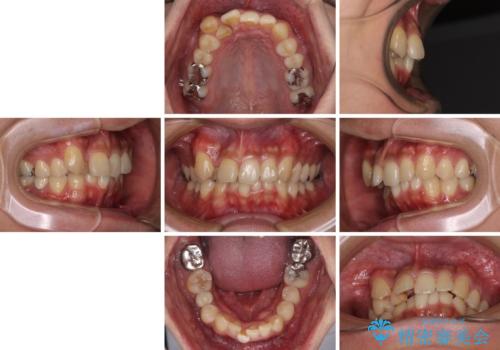

- 上顎の八重歯と正中のズレを気にして来院された患者様です。

八重歯による叢生は著しく、それにより上顎の正中が大きく右にずれている状態でした。

口元の突出感は感じていなかったことと、奥歯の咬み合わせを考慮し、上顎のみ左右の第一小臼歯を抜歯してワイヤー装置にて矯正治療を行うこととしました。

補助装置を併用することで効率的に八重歯や正中位置の改善を達成することができました。